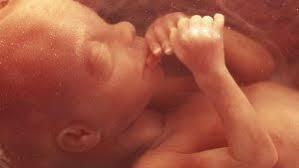

• 16º Semana

16º Semana

Etapa en la cual se sitúa el corazón del feto y también este desarrolla los sentidos y sus movimientos comienzan a ser perceptibles.